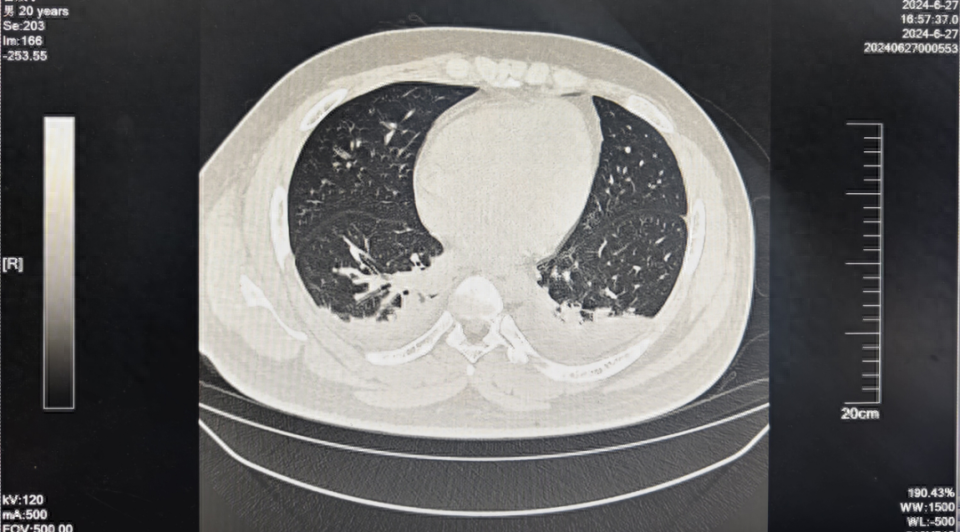

中毒后数日,在百草枯炎症风暴下,患者出现肝脏、肾脏等多脏器功能严重损伤。患者双肺出现了明显渗出,胸腔积液,导致双肺膨胀不全,具体表现为患者呼吸困难,血氧饱和度仅维持在90%,病情逐渐加重进展。

然而,患者双肺损伤不容乐观,胸部CT显示在胸腔积液的基础上,部分出现纤维化。